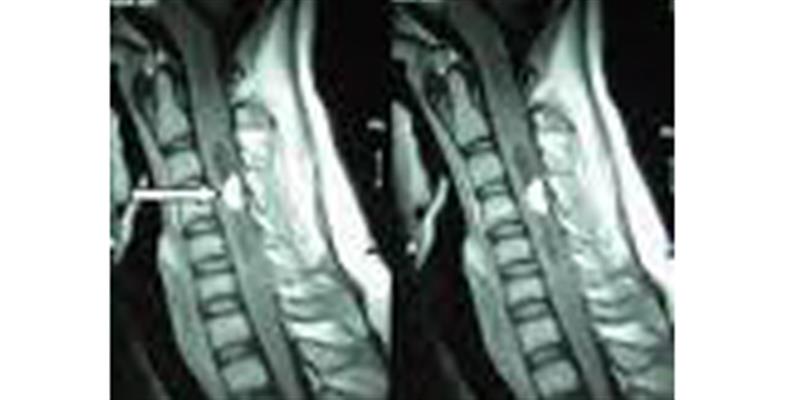

Spinal menengiomların genellikle iyi huyludurlar. Beyindeki menengiomalar gibi omurilik zarlarından kaynaklanırlar. Tüm spinal intradural tümörlerin % 25- 48 oluştururlar. 50- 60 yaşlarında en sık görülürler. Kadınlarda daha sık olup, 4-5/1 oranında görülürler. En sık torakal % 67-84, % 14- 27 servikal (boyun), % 2-14 lomber (bel) bölgesinde yerleşirler. Genellikle intradural yerleşimli iken, % 3-9 oranında ekstradural, %5-14 inradural ve ekstradural yerleşimli olabilirler. Ağrı en sık şikayeti olup, bunu duyu, motor, sphinkter şikayetleri takip eder. Bu tümörlerin teşhisi oldukça kolay olup günümüzün gelişmiş teşhis yöntemlerinden Magnetik rezonans (MR) kolaylıkla teşhisi konulmaktadır. Öncelikle muayeneyi yapan hekim aklına bir omurilik veya omurga tümörü öntanısı aklına getirsin. Bu tümörlerin tedavisi ise oldukça kolay ve yüz güldürücüdü ve başarılıdır. Cerrahi tedavide amaç tümörü kaynaklandığı yerden tamamını çıkartmaktır. Çok nadiren habis menengiomlar tipleri vardır. Bunlarda tekrarlama riski olup bunlara radyoterapi eklenir. Spinal menengiom cerrahisi komplikasyonları cerrahın tecrübesine göre oldukça düşüktür.

Sinir kılıfı tümörleri olup genel nufusda 100 000/ 0.3-0.5 gibi nadir görülen tümörlerdir. 30-50 yaşlarında sıktır. Kadın erkek oranı aynıdır. En sık torakal bölge olmak üzere burayı servikal ve lomber bölgeyi seçer. Bu tümörler de menengiomlar gibi yavaş yavaş büyürler başlangıçta ağrı bunu motor güçsüzlük ve duyu, sfinkter, sikayetleri takip eder. Bu tümörlerin teşhisi de aynı menengiomlar gibi oldukça kolay ve çabuk olarak MR sayesinde konulmaktadır. Tedavisi cerrahi çıkartmadır. Ameliyatında en önemli husus orijinlendiği sinir kökünü doğru tanıyıp bu kökle birlikte tümörün tamamını çıkartmaktır. Nüksler genellikle kısmı çıkartmalar sonucunda kaçınılmazdır. Cerrahi başarı cerrahın tecrübesi ile yakından ilgilidir. Sonuç genellikle mükemmeldir.